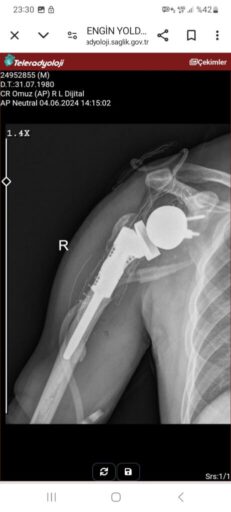

”3 sene önce Egepol hastanesinde iş kazası geçirdim engelli kadrosunda çalışıyordum . iş kazası geçirince orada ameliyatımı yapamadılar kol kaybetme riski olduğu için. Bende kendi doktoruma müracaat ettim orada ilk önce ters protez koydular uyum olmayınca bir sene sonra tekrar yeni bir ters protez koydular daha sonra Ankara’dan evraklar sunulup tümör protez için onay istendi onay geldikten sonra ameliyatımı oldum (haziran 4)

20 gündür omzum yerinden çıkmaya başladı doktoruma gittim doktorumda takılan parçanın ufak geldiğini ve derhal başlığın değiştirilmesi gerektiğini söyledi malzeme temini için hastanenin satın alma müdürlüğüne gittim, bu parçanın 2.kez ücretsiz karşılanamayacağını hastanenin başhekimi onay vermiyor diye söylediler. Benden ücret talep etmekteler benim durumum yok engelli bir vatandaşım 8 yaşında kızımda epilepsi kalp hastası ve tansiyon hastası. Hastane ve yönetimden şikayetçiyim.